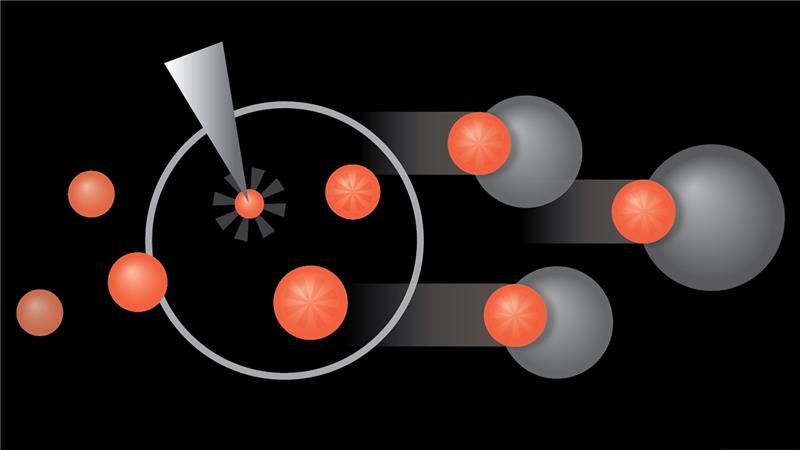

As part of the innate immune system, NK cells have a natural ability to recognize and eliminate GSCs. Engineering these cells can boost their fitness and antitumor activity. IL-21 is an immune signaling protein, or cytokine, shown to promote better metabolic fitness in NK cells.

In this study, first author Mayra Shanley, Ph.D., principal research scientist at MD Anderson, and her co-authors used multiple in vitro and in vivo models to treat GSCs with NK cells engineered to express either IL-21 or IL-15, another cytokine used to boost NK cell activity.

To accomplish this, they incorporated CD27, the natural receptor for CD70, into the CAR NK cells to bind CD70+ cancer cells. They also evaluated various costimulatory molecules, including CD28, paired with CD3ζ to enhance CAR NK cell activity. Finally, the cells also included IL-15 to improve NK cell persistence and iC9 as a safety switch, based on previous research findings.

The CAR NK cells with CD28 demonstrated high cytotoxicity against CD70+ tumor cells in vitro and in multiple tumor models of hematologic and solid tumors. CD28 consistently emerged as one of the top costimulatory molecules tested. After a closer look, the researchers discovered that CD28 activates key signaling pathways involving LCK, CD3ζ and ZAP70 in the CAR NK cells to enhance their anti-tumor activity.